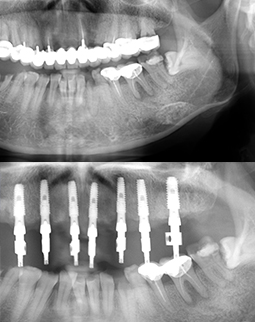

在给我戴临时冠之前,医生让我重新拍了CT,为了检测种植体植入的位置是否有便宜,咬合关系是否有出问题,通过牙片不得不说医生种的“很正”,种牙后我在用冰袋冷敷自己的创口,毕竟种牙的颗数有点多,要说一点不适感都没有那肯定是骗人的,哈哈。上面是我种牙之前的CT,下面是现在刚种完的,我还是很满意的,下面有两个看着发白的牙齿,是我下排根尖周炎的牙齿,后期再说治疗。